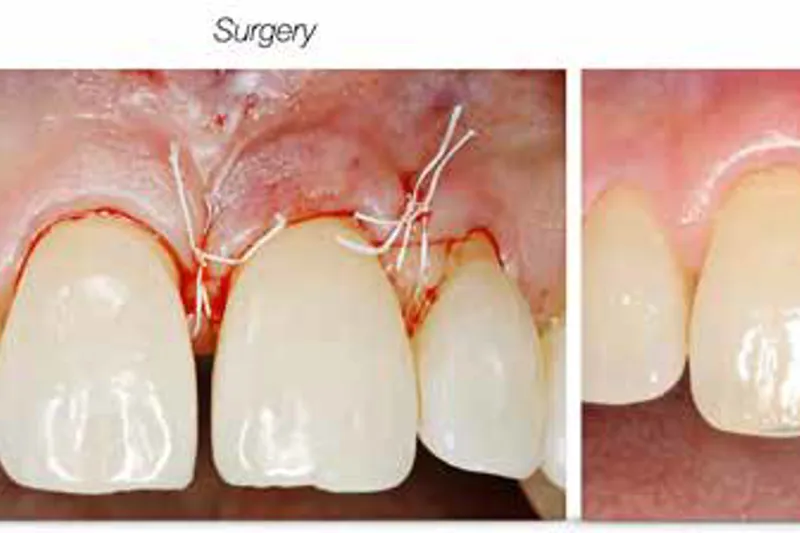

Kirurgisk parodontalbehandling er et af emnerne i de kliniske retningslinjer for behandling af parodontitis stadium I-III, som European Federation of Periodontology (EFP) for nylig har udgivet. På baggrund af fem systematiske oversigter kunne et internationalt panel af eksperter konkludere, at kirurgisk behandling er en særdeles relevant behandlingsmulighed, som bør overvejes, hvis der efter sufficient gennemført nonkirurgisk parodontalbehandling stadig forekommer restpocher på ≥ 6 mm. I de tilfælde, hvor restpocherne findes i tilknytning til intraossøse defekter på ≥ 3 mm, anbefaler retningslinjerne regenerativ behandling. EFP vurderer endvidere, at det kan være gavnligt at kombinere forskellige regenerative teknikker. Furkaturinvolvering på molarer er ikke i sig selv en indikation for ekstraktion af de ramte tænder. Hvis der er restpocher i tilknytning til Klasse II-furkaturinvolvering, anbefales regenerativ behandling. Ved Klasse III-furkaturinvolvering anbefaler retningslinjerne tunnelering eller rodresektion. EFP’s retningslinjer for behandling af parodontitis stadium I-III er i det store og hele i overensstemmelse med de tilsvarende retningslinjer fra de nordiske lande. Dog fraråder de nordiske retningslinjer kombination af flere regenerative procedurer, og de svenske og danske retningslinjer, der er af lidt ældre dato end de europæiske, finder ikke, at evidensen for brug af regenerativ behandling af furkaturinvolveringer er tilstrækkelig overbevisende til, at man kan anbefale denne behandling.

The recently published clinical practice guidelines on the management of stage I-III periodontitis by the European Federation of Periodontology (EFP) addressed surgical interventions. Based on findings presented in five systematic reviews, the panel of experts found surgical therapy to be an important tool to be considered after adequate non-surgical treatment, in particular at sites demonstrating residual pocketing ≥6 mm. In case residual pocketing was associated with an intra-bony defect with a depth of ≥3 mm, regenerative procedures were strongly recommended. The EFP considered the combination of regenerative techniques to be beneficial. Furcation involvement of molar teeth was found not to be a reason for tooth extraction per se. If residual pocketing was associated with furcation involvement class II, regenerative procedures were recommended. For furcation involvement class III, the guidelines recommended tunneling or root resection. EFP guidelines on the management of stage I-III periodontitis are largely in agreement with corresponding guidelines in Nordic countries. There is some disagreement in terms of combination of regenerative procedures, which is discouraged in Nordic guidelines. Further, Swedish and Danish guidelines have not found the evidence on the potential benefit of regenerative procedures of sites at furcation defects to be sufficient to recommend its use.